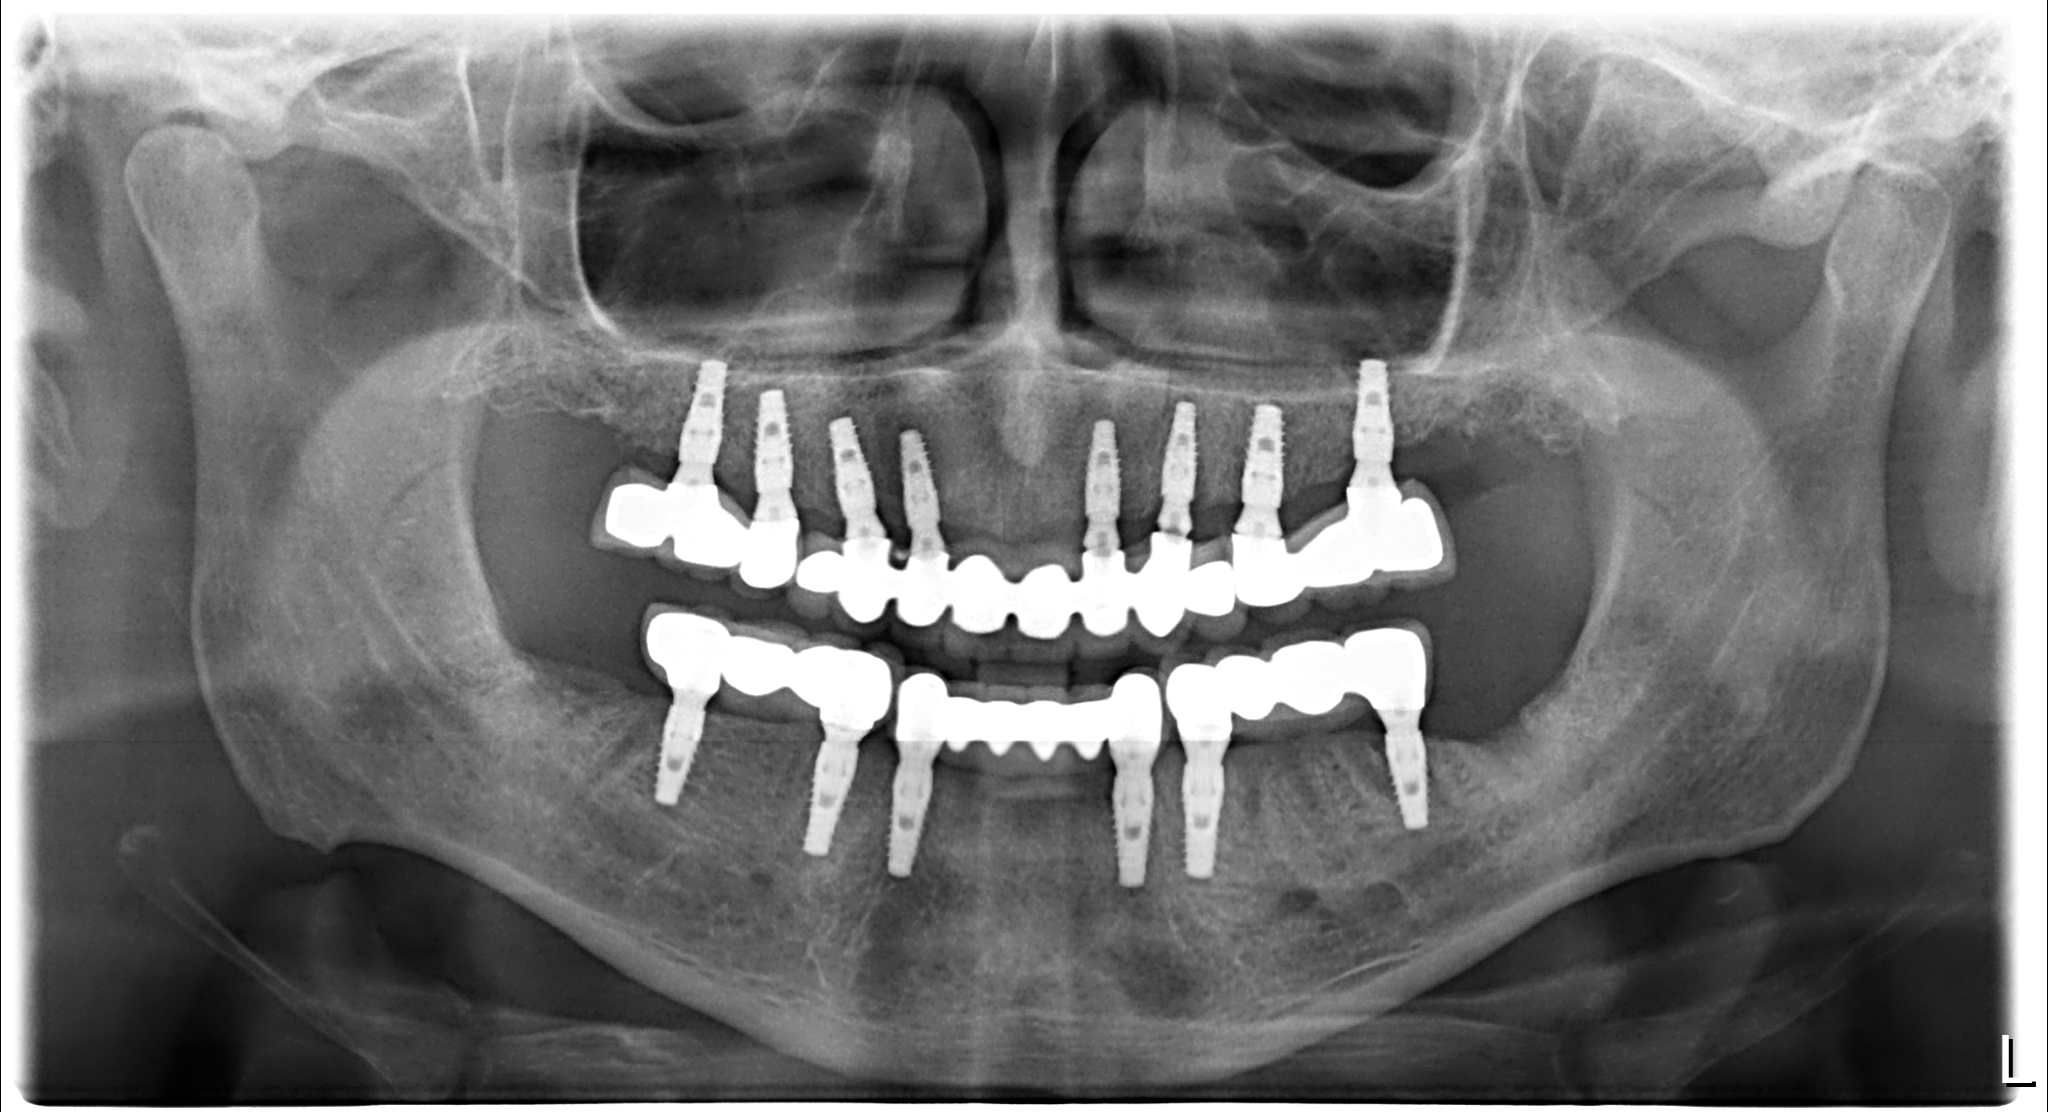

Six Naxis implants were successfully placed in the lower jaw, while eight were placed in the upper jaw. Following implant surgery, immediate healing abutments were used to expedite recovery and reduce the risk of infection.

Three months later, after the completion of implant osseointegration, the patient's need for prostheses was evaluated. Zirconium prostheses were preferred to meet the patient's aesthetic and functional requirements. Zirconium prostheses offer advantages in terms of durability and natural appearance.